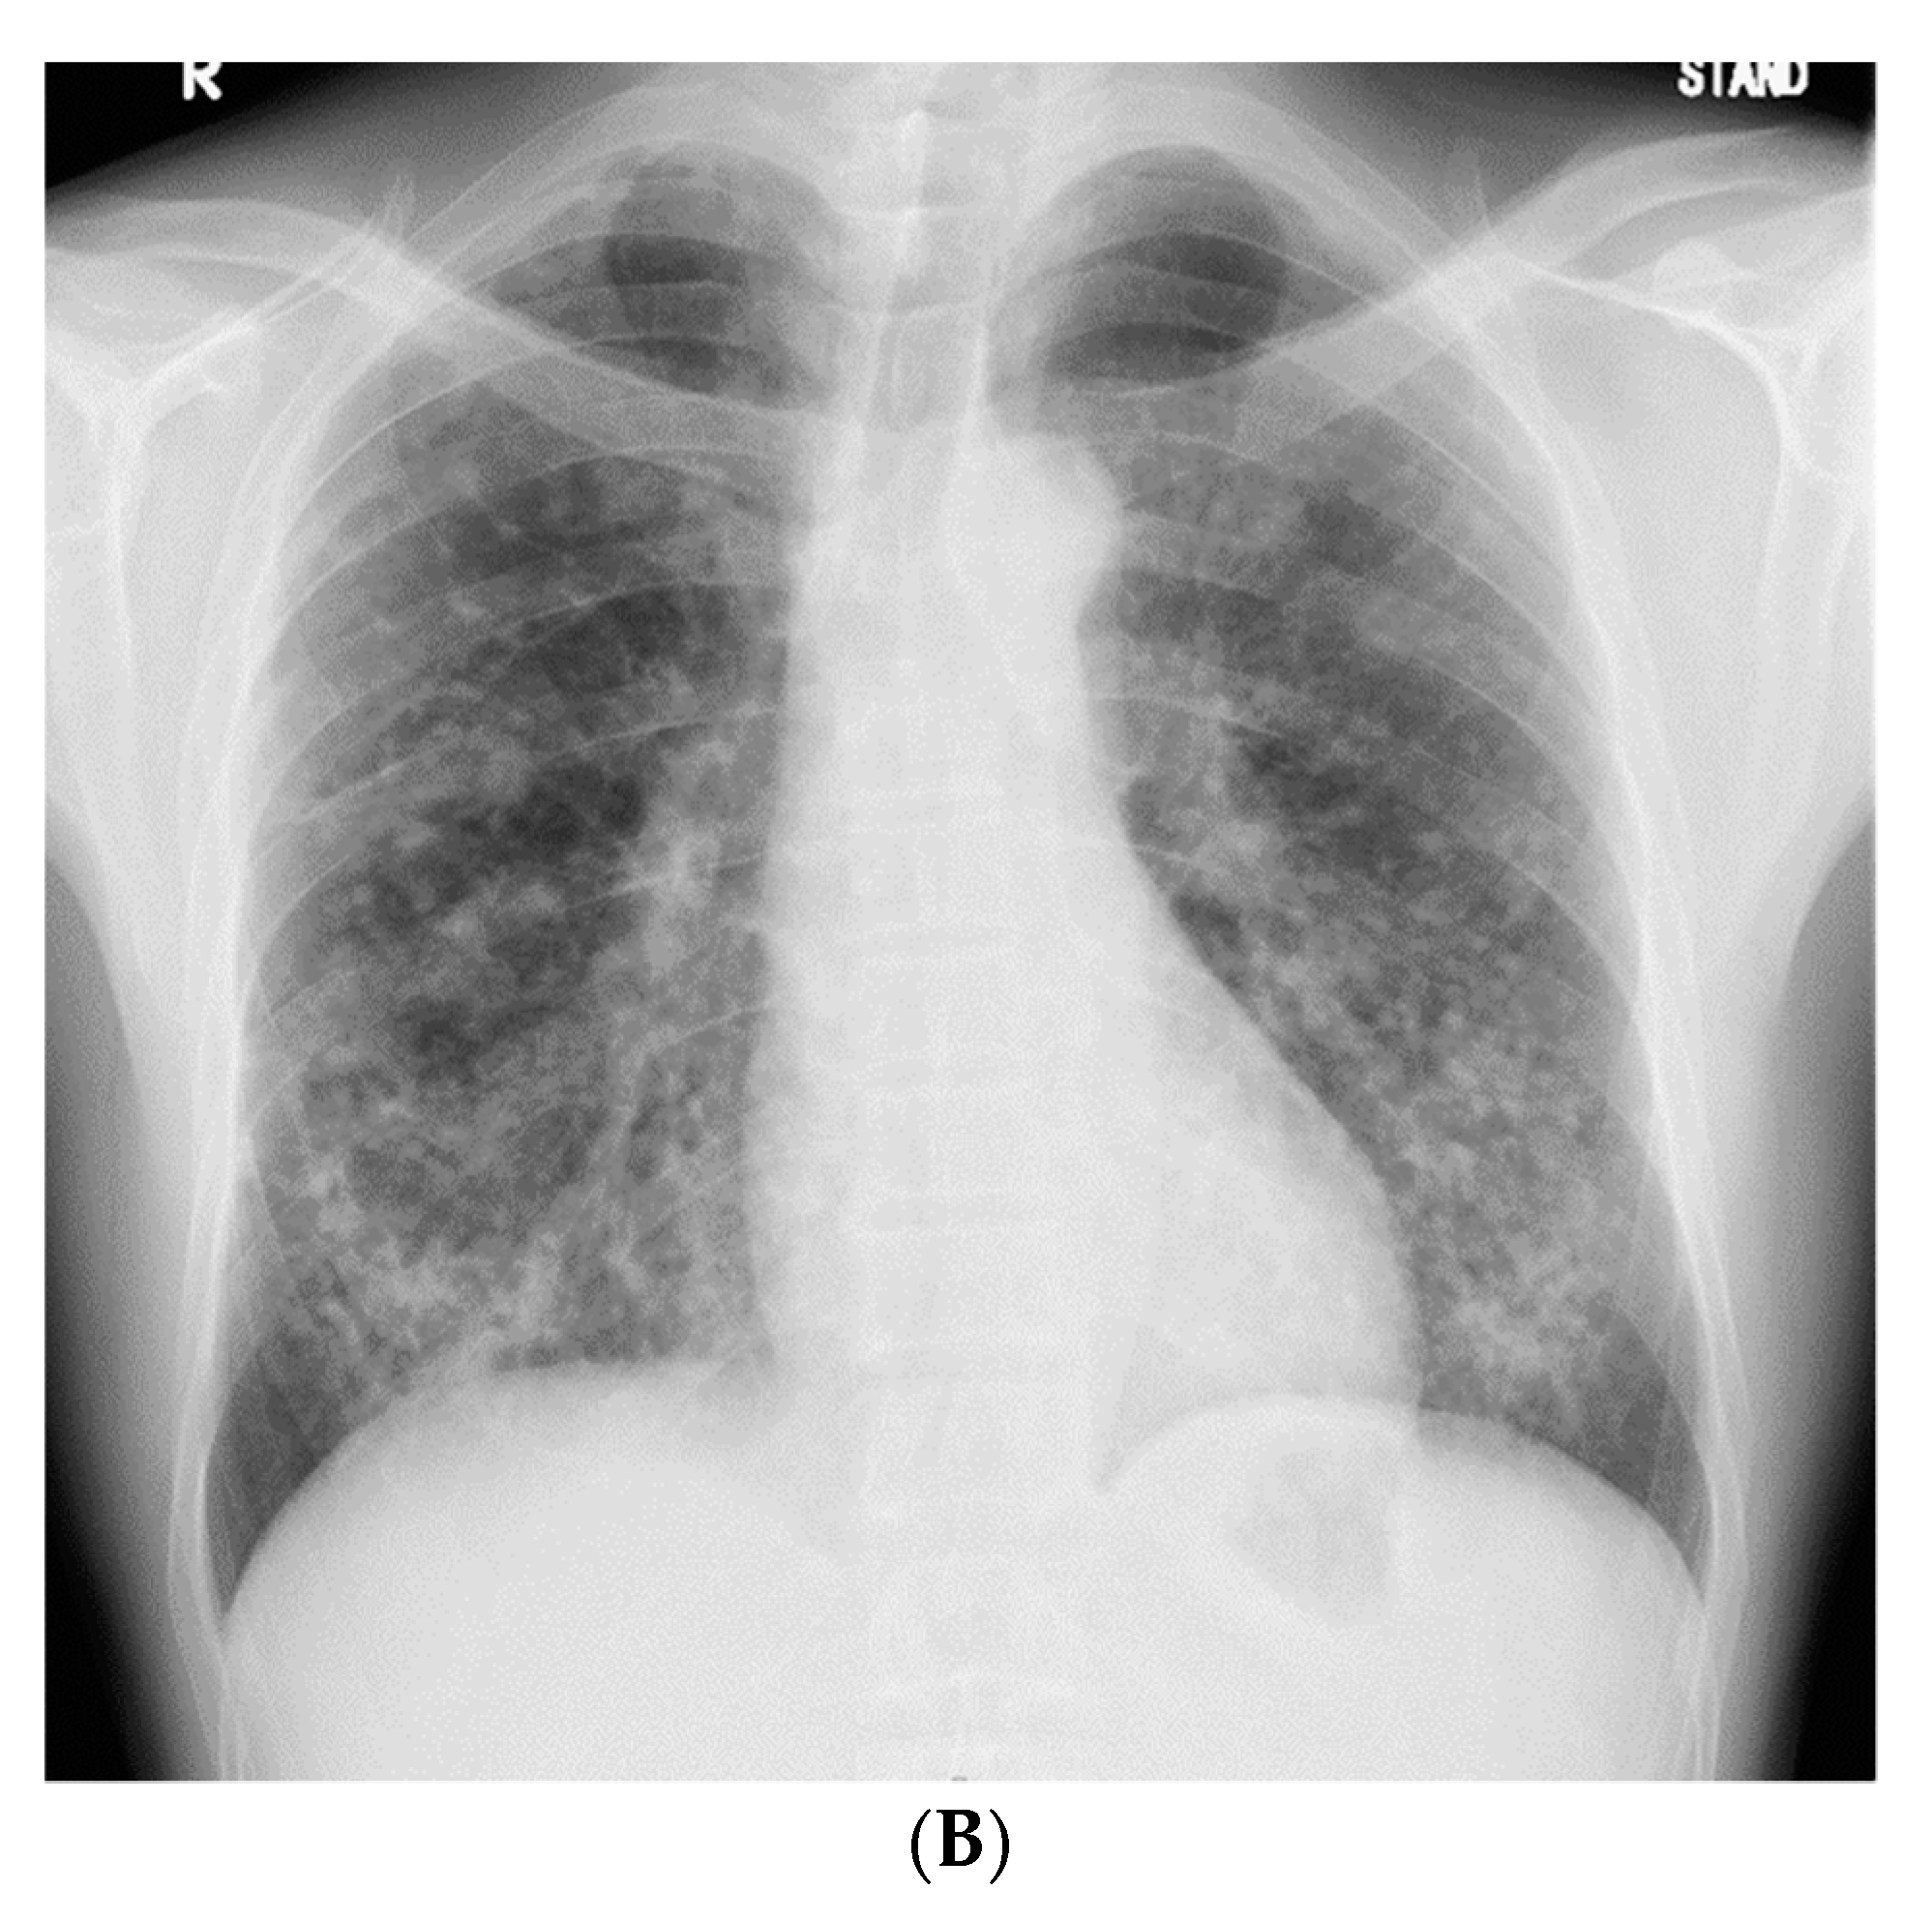

A 51-year-old, asymptomatic Japanese man with rapidly progressing nodular shadows, as observed on chest radiography performed as part of his routine physical examinations, was referred to our hospital. Two years ago, his chest radiograph had revealed no abnormalities. Small nodules had appeared a year later, mainly in both the lower lung fields (Figure 1A); however, he did not visit a hospital. Further, he reported a smoking history of 30 pack-years. As a civil engineer, he had been engaged in underground construction with welding, cutting, and drilling of reinforced concrete and metals for 10 years (between the ages of 41 and 51 years); though he had never used and/or been exposed to beryllium.

Figure 1.

(A) Chest radiograph 1 year prior to referral to our hospital, showing small nodules in both the lower lung fields. (B) Chest radiograph on admission, showing an increase in the number of nodules in 1 year.

The patient did not display clinical respiratory symptoms such as dyspnea, exercise intolerance, or any other relevant manifestations upon referral to our hospital. The patient’s body temperature, pulse rate, and respiratory rate were 36.9 °C, 58 beats/min, and 20 breaths/min, respectively. On chest auscultation, fine crackles were audible in the bilateral lower lung fields. Clubbed fingers were not observed. Laboratory data on admission revealed elevated levels of PR3-ANCA (15.4 U/mL, cutoff level: 3.5 U/mL). Other representative tests for collagen disease-related autoantibodies were negative. Serum levels of angiotensin-converting enzyme, carcinoembryonic antigen, KL-6, and sIL-2R were in the normal range, and the results of interferon-gamma release assay were negative. The chest radiograph on admission showed an increase in the number of nodules compared with those found 1 year previously (Figure 1B).